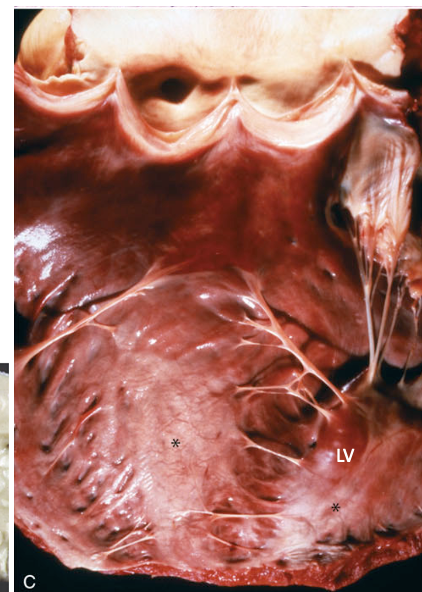

What is affecting these heart valves?

hematocyst (top) and lymphocyst (bottom)